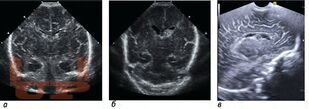

Внутрижелудочковые кровоизлияния у недоношенных новорожденных

В учебном пособии рассматривается проблема персонализации медицинской помощи недоношенным новорожденным с внутрижелудочковыми кровоизлияниями.

Учебное пособие предназначено для неврологов, неонатологов, нейрохирургов, врачей ультразвуковой диагностики и врачей других специальностей, участвующих в оказании медицинской помощи новорожденным с внутрижелудочковыми кровоизлияниями.